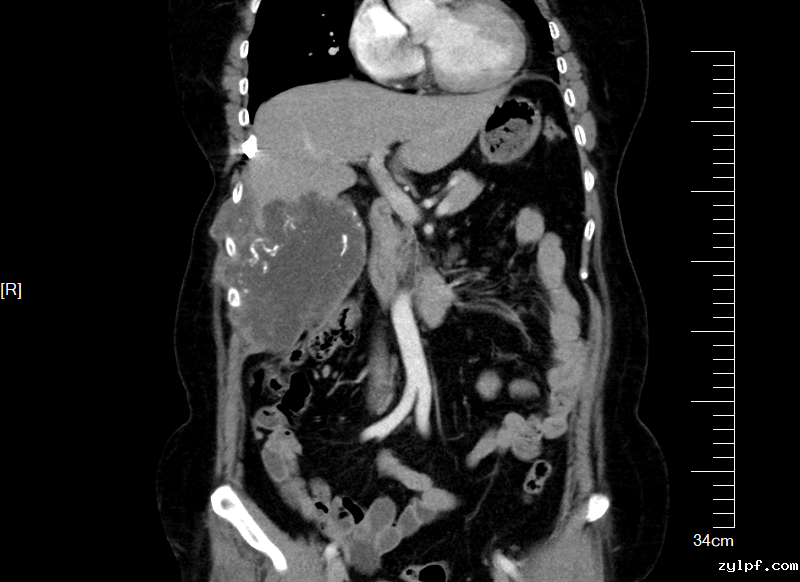

术前CT评估肿物与周围脏器关系,横截面与冠状面

影像检查显示,肿物起源于第7,8肋骨,沿胸腹壁蔓延累及第7至第11肋,上界与肝脏S5、S6段分界不清,内侧包膜紧贴右侧结肠,后方逼近右肾。“患者首次手术已切除部分肋骨,此次复发范围更广、侵袭更深,既要确保肿瘤完整切除(R0切除),又要最大限度保护重要脏器,需要多学科专家协作和新技术手段保驾护航。”骨科王伟东副主任在初次讨论时指出了本案例的关键节点。